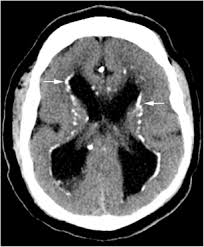

hot cross bun sign

hyperintensities of cerebellar peduncles